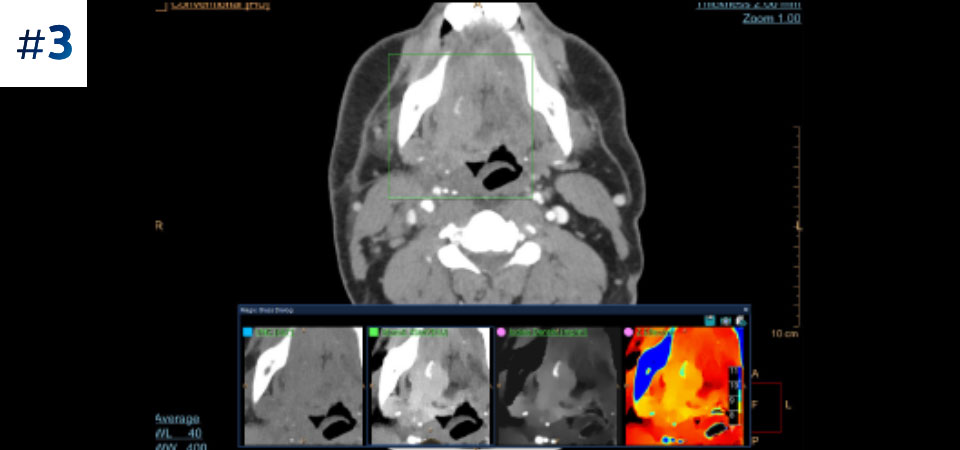

Massa do pescoço

Verifique aqui as suas respostas.